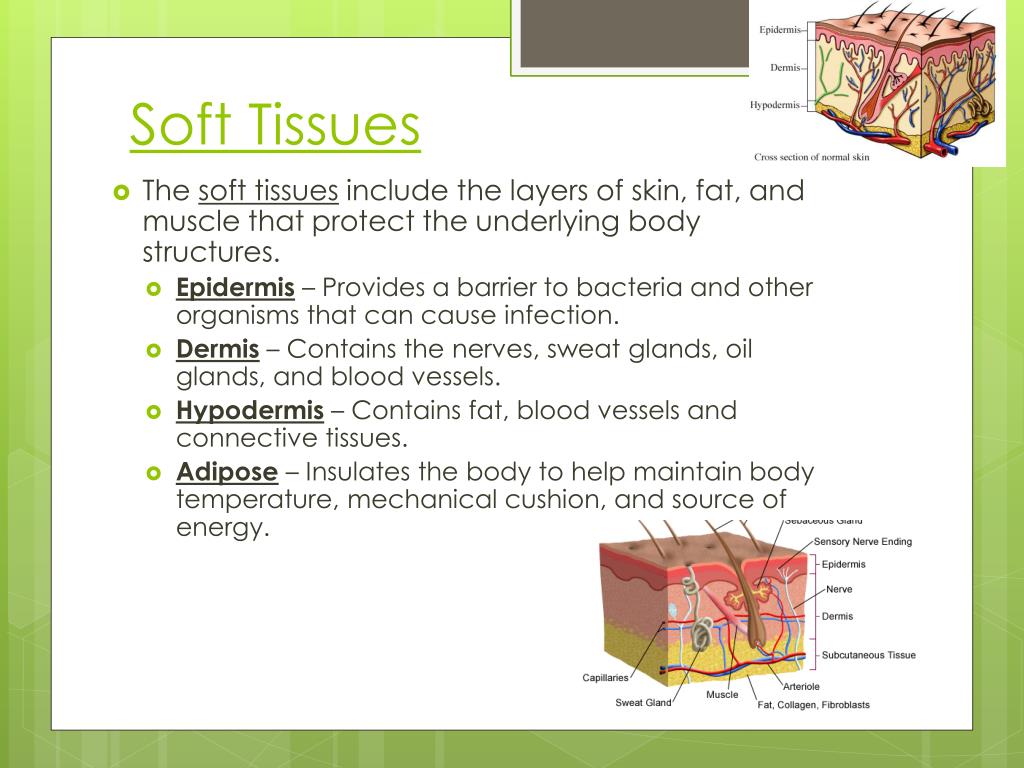

Soft Tissue Diagram

Soft Tissue Diagram

The 4 Types Of Tissue